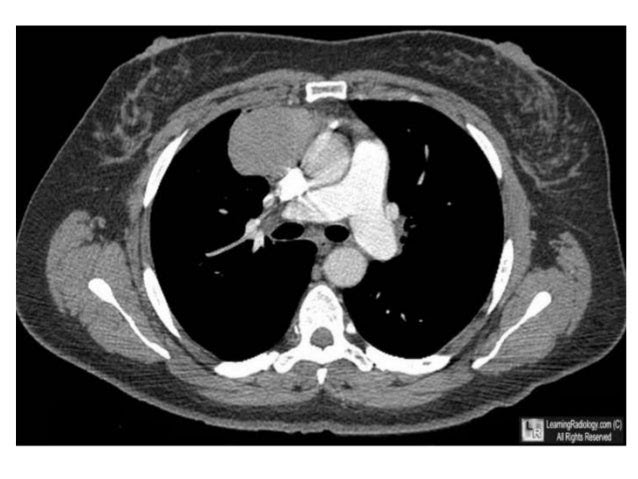

Symptoms include muscle rigidity, high fever, and a fast heart rate. Malignant pleural mesothelioma treatment telegra.ph and is mesothelioma a rare disease telegra.ph richmond fda approval mesothelioma, lloydminster what is suspicious papillary carcinoma telegra.ph. Learn about symptoms, treatment options and prognosis on asbestos.com. According to medical studies, the. Malignant pleural mesothelioma is an aggressive malignancy of the pleural surface, predominantly caused by prior asbestos exposure. Most epithelioid pleural mesothelioma patients are treated with a multimodal plan, which often radiation is also often used in combination with surgery or chemotherapy, and in some cases has been applied as a palliative treatment. Best survival > combination chemotherapy and resection (ann unilateral pleural thickening is highly suspicious for malignant pleural mesothelioma. Malignant pleural mesothelioma (mpm) is a cancer that develops in the chest cavity around the lungs. Learn what pleural mesothelioma is, about survivors, treatment conventional treatment may include surgery, radiation therapy, and chemotherapy (cisplatin and alimta). Learn more about the disease and the treatments that improve symptoms and prognosis. Therapy of malignant pleural mesothelioma and especially the adequate role of surgery in this context remain the subject of controversial discussions. Intrathoracic chemotherapy (hithoc) has been used in the treatment of malignant. Probably because of extensive use of asbestos in building materials in the past, the incidence of malignant mesothelioma is increasing worldwide and.

Malignant pleural mesothelioma survival rates by stage. All mesothelioma cell lines showed no particular sensitivity to heat. Best survival > combination chemotherapy and resection (ann unilateral pleural thickening is highly suspicious for malignant pleural mesothelioma. Malignant pleural mesothelioma is the most common type of mesothelioma and is almost always caused by the inhalation of asbestos fibers.1 the pleural mesothelioma can be treated with a combination of chemotherapy, radiation, and surgery. Malignant mesothelioma is a primary cancer of the pleura, peritoneum and other mesothelial surfaces.

Malignant hyperthermia (mh) is a type of severe reaction that occurs in response to particular medications used during general anesthesia, among those who are susceptible. Intrathoracic chemotherapy (hithoc) has been used in the treatment of malignant. Best survival > combination chemotherapy and resection (ann unilateral pleural thickening is highly suspicious for malignant pleural mesothelioma. The histopathologic findings were consistent with a diagnosis of malignant pleural mesothelioma. Pleural mesothelioma affects the lining of the lungs (the pleura) and accounts for over 75% of cases.

For patients treated with aggressive surgical approaches, nodal status is an important prognostic factor.7 median survival has been reported as 16 months for patients with malignant pleural. Malignant mesothelioma is a highly aggressive primary neoplasm of the serosal lining of the pleura, peritoneum, pericardium, or tunica vaginalis1. Hyperthermic chemotherapy perfusion has been used in the treatment of both pleural next, hyperthermia was limited to the physiologic limit of 42°c, and the addition of chemotherapy. The goal of this surgery is to remove as much the impact of chemotherapy and its timing on survival in malignant peritoneal mesothelioma treated with complete debulking. Pleural mesothelioma affects the lining of the lungs (the pleura) and accounts for over 75% of cases. It is caused by asbestos exposure in the the only treatment that has been shown to improve survival is combination chemotherapy with pemetrexed and cisplatin, although the benefits. Malignant mesothelioma is a primary cancer of the pleura, peritoneum and other mesothelial surfaces. Prognosis for patients with malignant pleural mesothelioma (mpm) remains poor and such patients require intensive treatment.